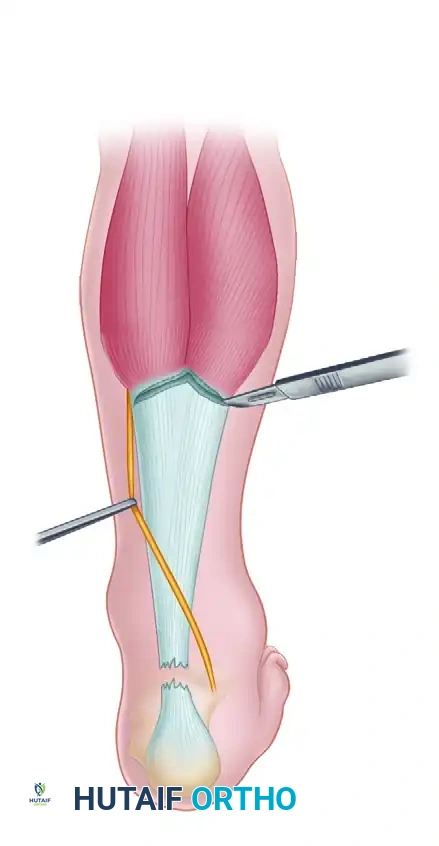

Step-by-Step V-Y Advancement

Incision and Exposure: A standard posteromedial incision is utilized to expose the ruptured ends. The fibrotic scar tissue is radically excised back to healthy, organized collagen bundles.

Design of the V-Flap: Proximal to the rupture, an inverted "V" incision is made through the gastrocnemius aponeurosis. The apex of the "V" is directed proximally. The length of the arms of the "V" must be at least 1.5 to 2 times the length of the defect to allow adequate distal excursion.

Advancement and Y-Repair: The aponeurotic flap is advanced distally, bridging the defect. The proximal "V" defect is then closed in a "Y" configuration. The advanced distal end of the flap is anastomosed end-to-end with the distal Achilles stump using heavy, non-absorbable core sutures (e.g., Krackow technique).

- FHL Retrieval: Incise the deep fascia longitudinally over the posterior compartment to expose the FHL muscle belly and tendon. Retrieve the tagged FHL tendon from the midfoot, pulling it proximally into the posterior wound.

- Weaving: Pass the FHL tendon through the tunnel, then route it proximally. Weave the FHL tendon from distal to proximal through the remaining substance of the Achilles tendon (or the aponeurosis) using a tendon weaver. Continue weaving until the full length of the harvested FHL tendon is utilized.